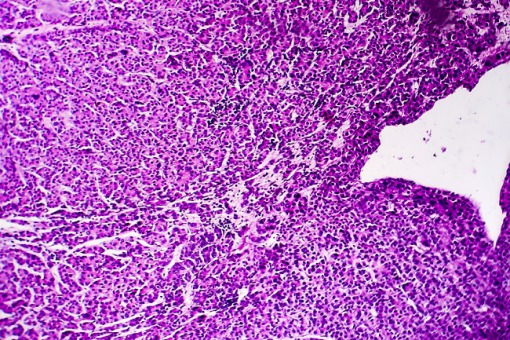

W trakcie XXII-giego Światowego Kongresu Nowotworów Układu Pokarmowego ogłoszono rozpoczęcie badania LEAP-012 oraz przedstawiono protokół badania. W tym projekcie naukowym, pacjenci z rakiem wątrobowokomórkowym u których nie można uzyskać radykalnej resekcji będą poddani leczeniu systemowemu opartemu o lenwatinib i pembrolizumab oraz dodatkowo chemoembolizacji przeztętniczej.